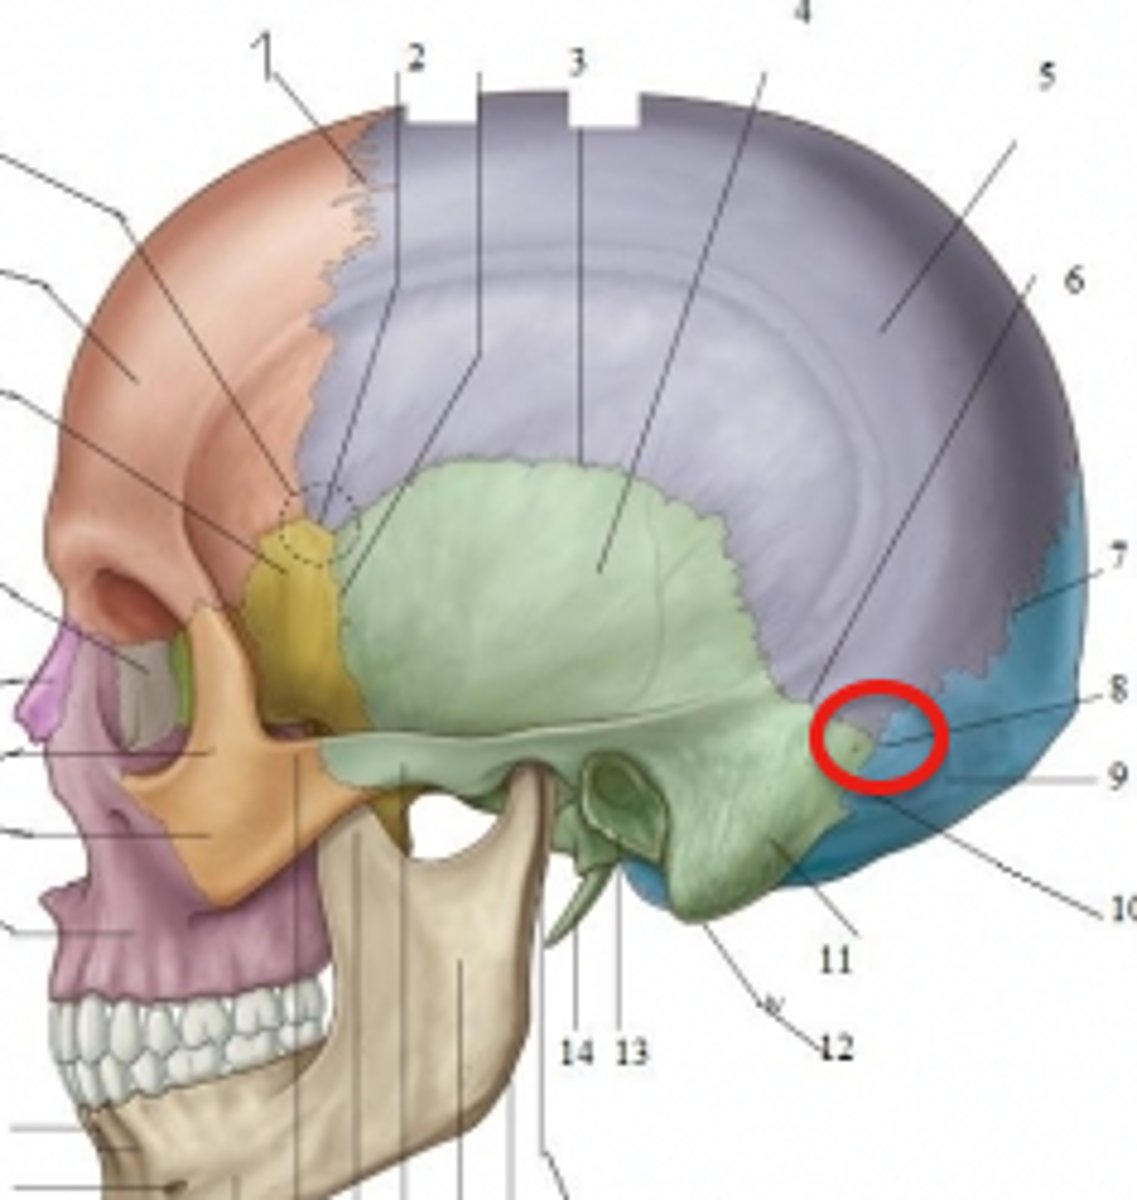

squamosal suture

asterion

What is 4?